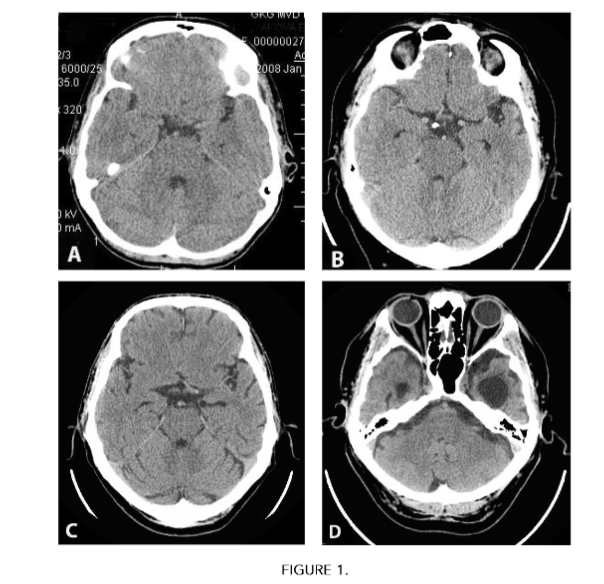

- preclinical stage of AD – TDR-0 – 10 (10.75%) people. In patients of this group, involutional changes in the brain are manifested by atrophy of the temporal lobes with a decrease in tissue mass by 4–8%; there is no dementia, but there are increasing memory disorders; cognitive functions are reduced to 26–28 MMSE points. Each of these patients had direct relatives suffering from AD (Fig. 1A), (Table 1);

- mild stage of AD – TDR-1 – 26 (27.96%) people. In patients of this group, involutional changes in the brain are manifested by atrophy of the temporal lobes with a decrease in tissue mass by 9–18%; mild dementia, corresponding to CDR-1; cognitive functions are reduced to 20–25 MMSE points. History of the disease is 2 years (Fig. 1B), (Table 1);

- moderately severe stage of AD – TDR-2 – 40 (43.01%) people. In patients of this group, involutional changes in the brain are manifested by atrophy of the temporal lobes with a decrease in tissue mass by 19–32%; moderate dementia, corresponding to CDR-2; cognitive functions are reduced to 12–19 MMSE points. History of the disease is 2–6 years (Fig. 1C), (Table 1);

- severe AD stage – TDR-3 – 17 (18.28%) people. In patients of this group, involutional changes in the brain are manifested by atrophy of the temporal lobes with a decrease in tissue mass by 33–62%; severe dementia, corresponding to CDR-3; cognitive functions are reduced to 7–11 MMSE points. History of the disease is 7–12 years (Fig. 1D), (Table 1).

FIGURE 1

CT scans of the brain of patients with different AD stages according to The Tomography Dementia Rating scale.

A – preclinical stage TDR-0, decrease in tissue mass of the temporal lobes: on the right by 7%, on the left by 8%.

B – mild stage TDR-1, decrease in tissue mass of the temporal lobes: on the right by 9%, on the left by 14%.

C – moderately severe stage TDR-2, decrease in tissue mass of the temporal lobes: on the right by 19%, on the left by 22%.

D – severe stage TDR-3, decrease in tissue mass of the temporal lobes: on the right by 41%, on the left by 58%

As in our earlier works¹³,³⁶,³⁷, this study showed that in AD the severity of dementia depends on the severity of atrophic changes in the cerebral temporal lobes. According to the digital morphometric scale “The Tomography Dementia Rating scale” (TDR), at the preclinical stage of AD (TDR-0), cerebral involutional changes are manifested in a decrease in the tissue mass of the temporal lobes by 4–8% of normal volume (Fig. 1(A)). In mild AD stage (TDR-1), temporal lobe atrophy is 9–18% (Fig. 1(B)), in moderate AD stage (TDR-2), temporal lobe atrophy is 19–32% (Fig. 1(C)), in severe AD stage (TDR-3), temporal lobe atrophy is 33–62% (Fig. 1(D)), (Table 1).